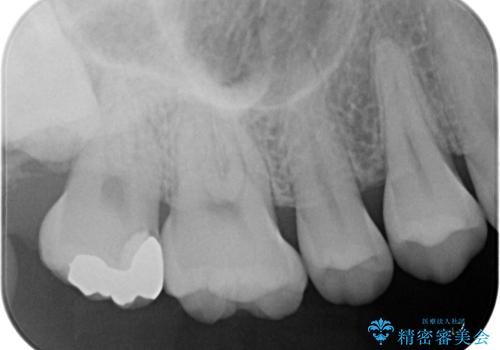

- 他院で虫歯があると言われたので診てほしいとのことで来院された患者様です。来院時特に症状もなく、レントゲンにて右上7に虫歯を認めました。

ゴールドインレーとセラミックインレーで迷われていたので両方のメリット、デメリットを説明してゴールドインレーで治療を進めていくこととなりました。

拡大鏡視野下で虫歯を除去し、ゴールドインレーに適した形に整えました。

歯と歯茎の間に圧排糸と言われる糸を入れてシリコーン印象材にて型どりをしました。

ゴールドインレー(PGAインレー)はセラミックインレーと比べ、歯の切削量が少なく、適合性が著しくいいことが特徴です。上顎の奥歯は見えないので機能面でゴールドインレー、ゴールドクラウンはおすすめです。

違和感がないと喜んでいただきました。